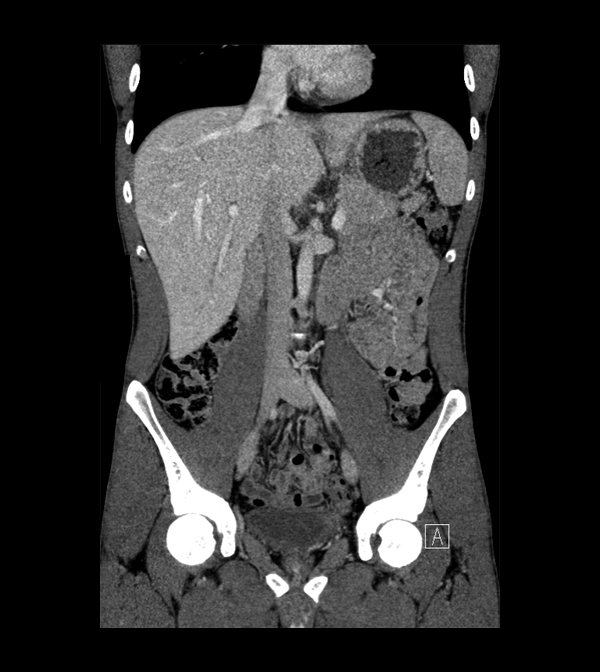

Body

Covers abdominal CT anatomy.